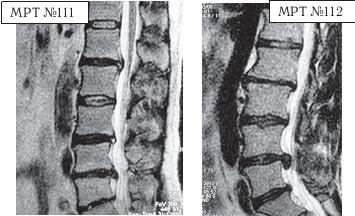

На МРТ № 111 поясничного отдела позвоночника отмечается рецидив — грыжа межпозвонкового диска LIV-LV после трёх операций. Даже если прооперировать в четвёртый раз, то это всё равно не решит проблемы и не добавит здоровья данному пациенту, так как неизбежно возникнут осложнения в вышележащих сегментах LI—LII LIII—LIV в силу биомеханических нарушений в позвоночнике и выраженных дегенеративно-дистрофических изменений в указанных сегментах. На МРТ № 112 поясничного отдела позвоночника отмечается рецидив — секвестрированная грыжа межпозвонкового диска в сегменте LIV-LV после четырёх операций. Здесь, как говорится, без комментариев. К сожалению, в жизни бывает так, что даже профессиональный специалист иногда вместо пользы может принести серьёзный вред пациенту, исключительно из-за шаблонного подхода. Как ни парадоксально это звучит, но это так. Приведу один пример по этому поводу. Ко мне на приём привели женщину. Привели в буквальном смысле этого слова под руки, при этом она ещё дополнительно опиралась на тросточки. Первое о чём я подумал, когда увидел, с какой осторожностью её ведут и как она переставляет ноги, что у данной пациентки как минимум перелом позвоночника с травмой спинного мозга или как максимум — опухоль в спинномозговом канале. Но в данном случае причина оказалось совсем иной. На протяжении последних десяти лет у пациентки периодически возникали боли в поясничном отделе позвоночника. Она к ним привыкла и не переживала по этому поводу, так как боли были умеренные, быстро проходили и довольно легко переносились. Но полтора года назад, после физической нагрузки, появились сильные, тянущие боли в ноге. Женщина вынуждена была обратиться в больницу по месту жительства. Пациентку направили к невропатологу, который, осмотрев её, сделал предположение, что возможно у неё «грыжа межпозвонкового диска» и направил женщину на МРТ. Так вот, сделав МРТ (МРТ №№ 113–115), женщина вернулась со снимками к невропатологу. Он ознакомился с результатами обследования и вместо того чтобы назначить ей консервативные методы лечения при таком диагнозе, направил её… на консультацию к нейрохирургу. Нейрохирург между прочим специалист высокого класса, с большим опытом работы, спасший много человеческих жизней. Однако и он, ознакомившись с результатами обследования, осмотрев пациентку, сделал вывод, что необходима срочная операция по удалению грыжи межпозвонкового диска в сегменте LIV-LV.